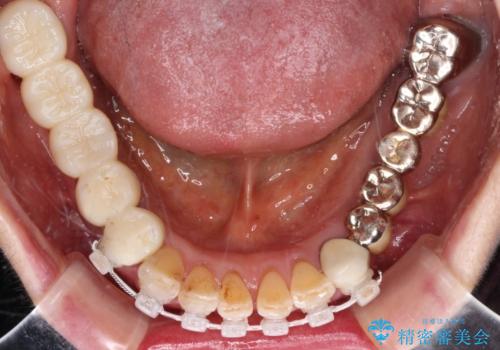

処置を予定していた歯を仮歯に変えた時点で、下顎前歯の部分矯正を行うかどうかを尋ねたところ、折角なので行いたいと言うことでしたので、矯正治療を行うこととしました。

インプラント埋入や根管治療治療など、治癒に一定の期間を要する処置の合間に矯正治療を行うことで、効率的に治療を進めて行くことができました。